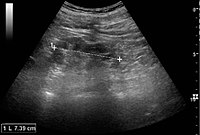

Ultrasound[edit | edit source]

Kidney ultrasonography is useful for diagnostic and prognostic purposes in chronic kidney disease. Whether the underlying pathologic change is glomerular sclerosis, tubular atrophy, interstitial fibrosis or inflammation, the result is often increased echogenicity of the cortex. The echogenicity of the kidney should be related to the echogenicity of either the liver or the spleen (Figure 22 and Figure 23). Moreover, decreased kidney size and cortical thinning are also often seen and especially when disease progresses (Figure 24 and Figure 25). However, kidney size correlates to height, and short persons tend to have small kidneys; thus, kidney size as the only parameter is not reliable.[44]